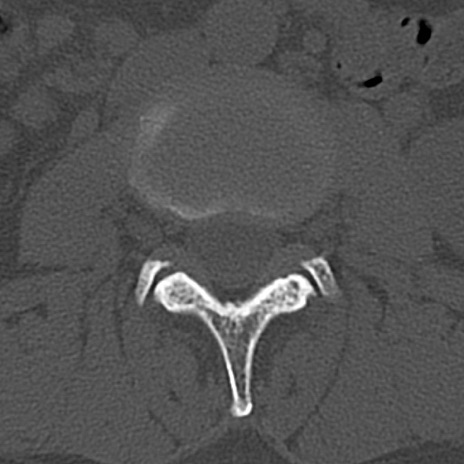

腰椎CT

横断像と矢状断像